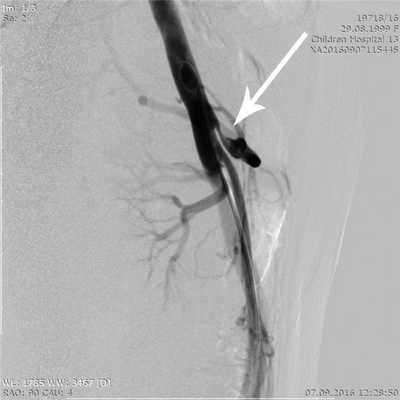

Повреждений ВСА при адекватном и своевременном использовании ультразвукового датчика не отмечено. Однако одно ранение ВСА все-таки произошло - при попытке удаления невриномы тройничного нерва из латерального расширенного транссфеноидального эндоскопического доступа (1,9% от всех случаев, в которых использовалась УЗДГ). В данном наблюдении перед вскрытием ТМО в латероселлярном пространстве проведено ультразвуковое исследование зоны разреза в проекции кавернозного синуса - артерии обнаружено не было. В безопасной, лоцируемой области выполнено вскрытие ТМО, после чего была визуализирована опухоль. Перед началом ее удаления, разрез ТМО решено было продолжить продольно вверх на 3 мм, в ту зону, где дополнительное лоцирование сонной артерии не проводилось, что и послужило причиной повреждения ВСА. Интенсивное артериальное кровотечение удалось остановить путем тугой тампонады полости носа гемостатическими материалами (Тахокомб, гемостатическая губка, марлевая турунда), после чего была выполнена каротидная ангиография, выявившая дефект в области переднего колена кавернозного сегмента правой ВСА. Одномоментно была выполнена эндоваскулярная окклюзия правой ВСА микроспиралями. В послеоперационном периоде у пациентки отмечен транзиторный парез VI черепно-мозгового нерва, в остальном неврологический статус отрицательной динамики не имел.